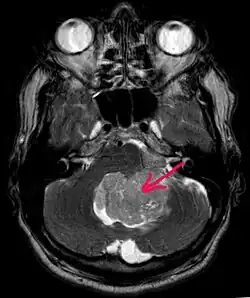

В типичных случаях на МРТ эпендимомы видны в виде объёмных образований, которые заполняют, а иногда и полностью тампонируют полость IV желудочка и распространяются в большую затылочную цистерну или боковую цистерну моста. Солидная часть новообразования на Т1-взвешенных томограммах выглядит изо- или даже гипоинтенсивной и гиперинтенсивной на Т2-взвешенных томограммах[24].

Дифференциальная диагностика эпендимом с другими глиомами основывается в основном на их локализации и топографии, а не на различиях интенсивности сигнала или степени контрастного усиления[25]. Кистозный компонент имеет гипоинтенсивный сигнал на Т1-взвешенных МРТ и гиперинтенсивный по отношению к мозгу на изображениях, взвешенных по Т2. Гетерогенность структуры опухоли обусловлена наличием кист, петрификатов, опухолевой сосудистой сети. После введения контраста отмечается негомогенное усиление средней интенсивности[26]. Дифференциальную диагностику эпендимом боковых желудочков необходимо проводить с медуллобластомами и астроцитомами[23].